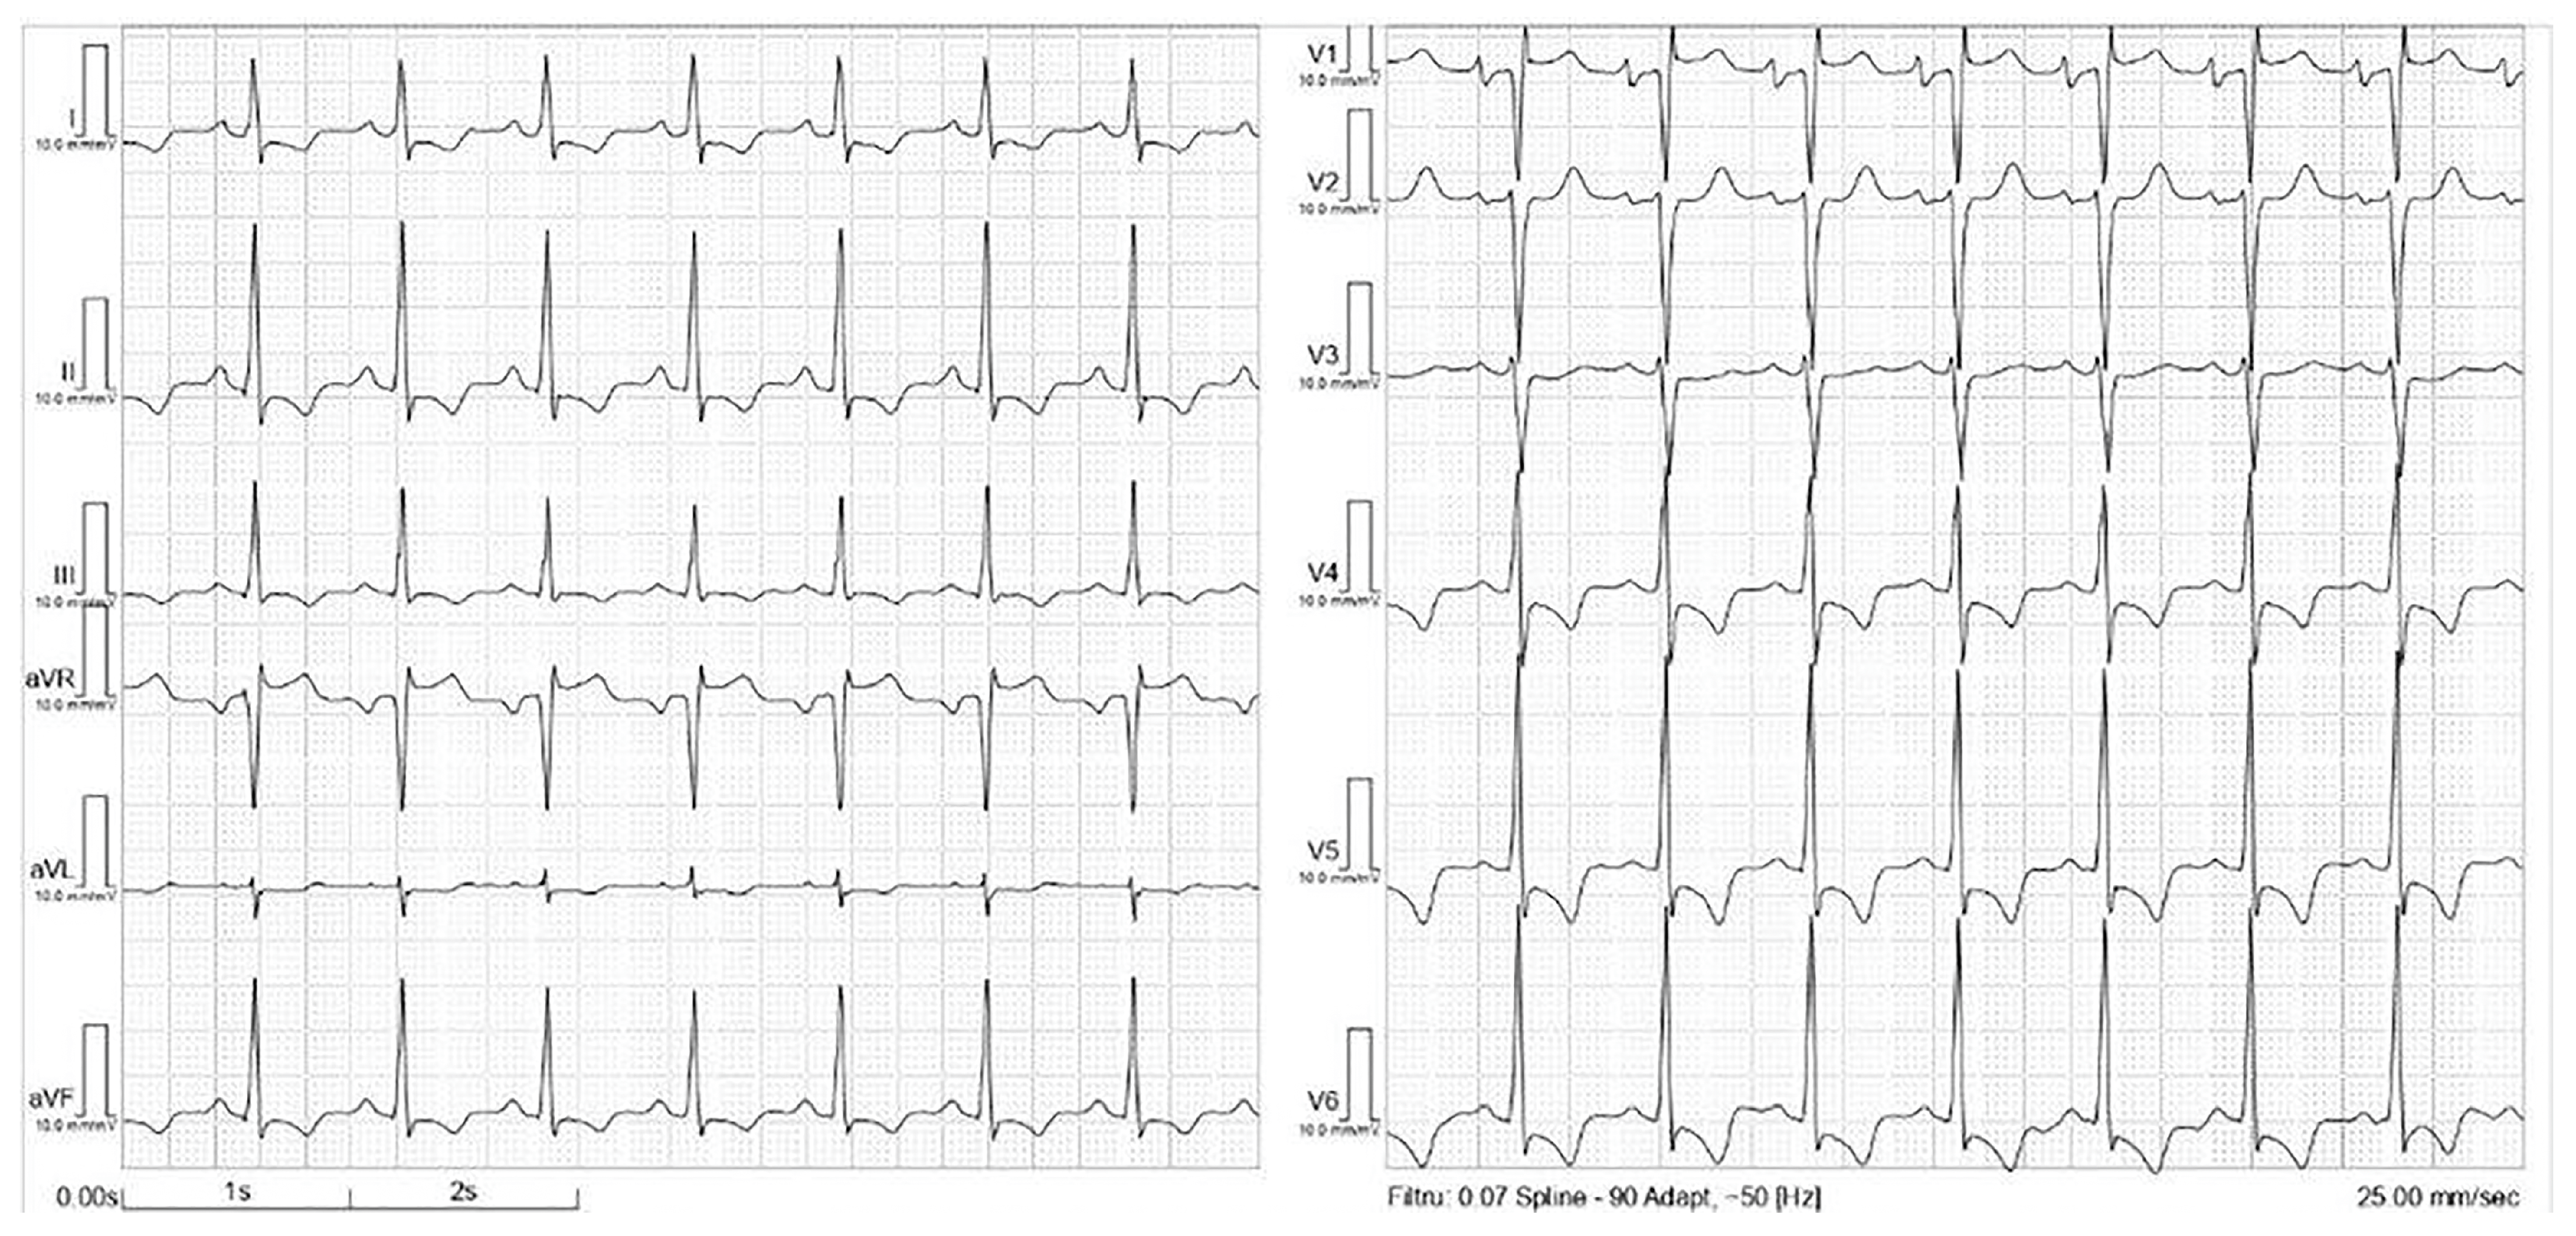

2. Case Presentation